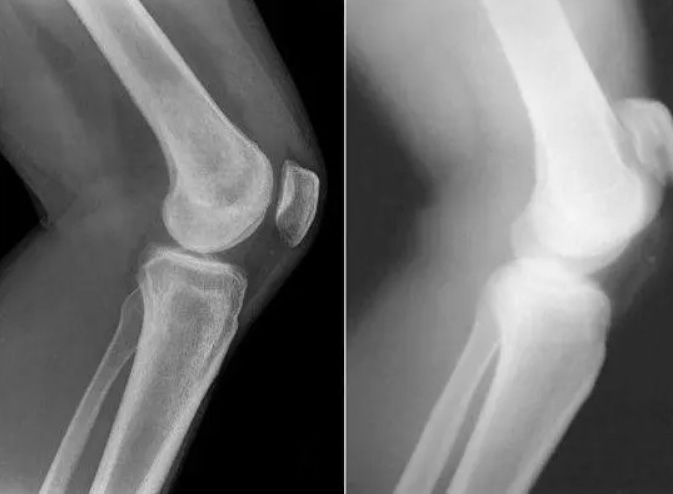

Femme de 54 ans. Son articulation est entièrement restaurée. La durée du traitement : 14 jours :

Restauration de l'articulation du coude. Patiente, 31 ans. Durée du traitement par la Marukaya Cream : 12 jours. Son articulation est entièrement restaurée :